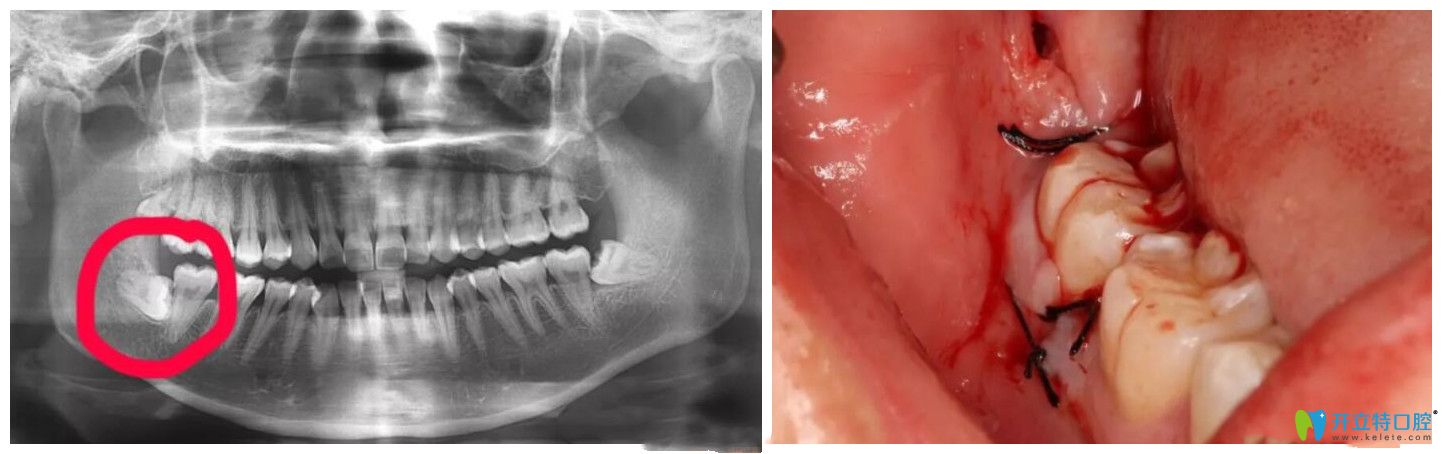

超聲骨刀拔牙真實(shí)案例

▲超聲骨刀拔牙真實(shí)案例